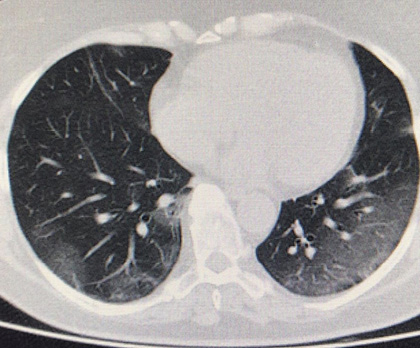

Routine clinical laboratory assays were performed in the hospital’s clinical laboratories. Clinical and laboratory information was extracted from the patients’ medical records. C reactive protein (CRP) in plasma was measured by immunoturbidimetry (Beckman Coulter, Krefeld, Germany). Interleukin-6 (IL-6) levels in plasma were measured by electrochemiluminescence (Siemens Medical Solutions Diagnostics, Siemens Healthcare, Erlangen, Germany). CT scans were read by experienced radiologists who scored results by severity using the criteria shown in Figure 1.

Figure 1. Clinical assessment of pneumonia severity based on computed tomography (CT) scores.

Scoring method: Mild (CT-1)—no more than three ground-glass opacities of <3 cm maximum diameter. Moderate (CT-2)—more than three ground-glass opacities; less than 50% involvement by visual assessment. Medium-heavy (CT-3)—ground-glass opacities and pulmonary consolidation; 50-70% involvement by visual assessment. Severe (CT-4)—diffuse ground-glass opacities with or without consolidation; more than 75% involvement by visual assessment.